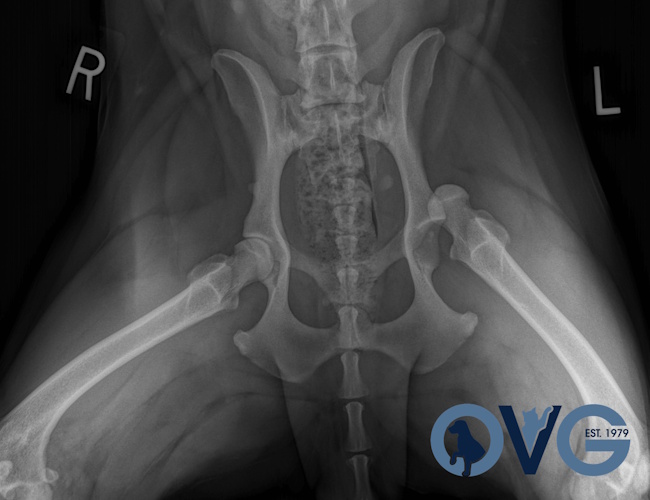

Hip Dysplasia

Hip Dysplasia in canines

Surgical Treatments of Hip Dysplasia

- Juvenile Pubic Symphysiodesis (JPS)

- Triple Pelvic Osteotomy (TPO)

- Total Hip Replacement (THR)

- Femoral Head and Neck Excision (FHNE)